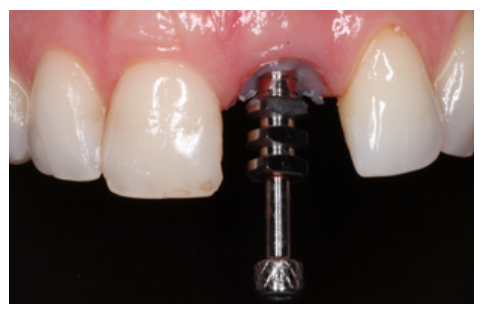

Clinical case: A 32-year-old female patient who attended for a possible root fracture of the upper left central incisor (ULCI), accompanied by a periodontal abscess at the bottom of the vestibule of the same tooth. A clinical and radiological examination established that the prognosis of the ULCI was unfavourable for conservative treatment. After evaluating the clinical features of the case, the treatment plan to extract the ULCI followed immediately by an osseointegrated implant (OII) and loading of a provisional prosthesis on the implant.

The benefits of immediate loading include a marked reduction in surgical interventions, less temporary dilation of the treatment and even better psychological and social wellbeing for the patient. In cases with a significant aesthetic requirement, immediate loading or provisionalisation, and post-extraction placement of the OII minimise alterations due to tooth loss and maintain the emergence profile, soft tissue contour and gingival papillae5-7.

Different protocols have also been established for the management of the anterosuperior aesthetic sector, in addition to performing the immediate implant and provisional crown, including placing material between the OII and the buccal cortical to minimise possible collapse and the management of peri-implant soft tissue8-11.